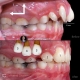

ارتودنسی دختر ۱۵ ساله با دندان نیش بیرون زده، انحراف میدلاین و کنت اکلوزال در مدت ۲۰ ماه انجام شد. به وجود آمدن انحراف میدلاین و کنت اکلوزال به علت جایگاه دندان نیش بیرون زده میباشد که در سنین پایین تر در مرحله دندانی مختلط میتوانست قابل پیشگیری باشد.

Orthodontic treatment of 15 years old girl with blocked out canine, midline shift and occlusal cant done within 20 months. The reason for occurrence of midline shift and occlusal cant was because of blocked out canine which could have been prevented in mixed dentition stage.